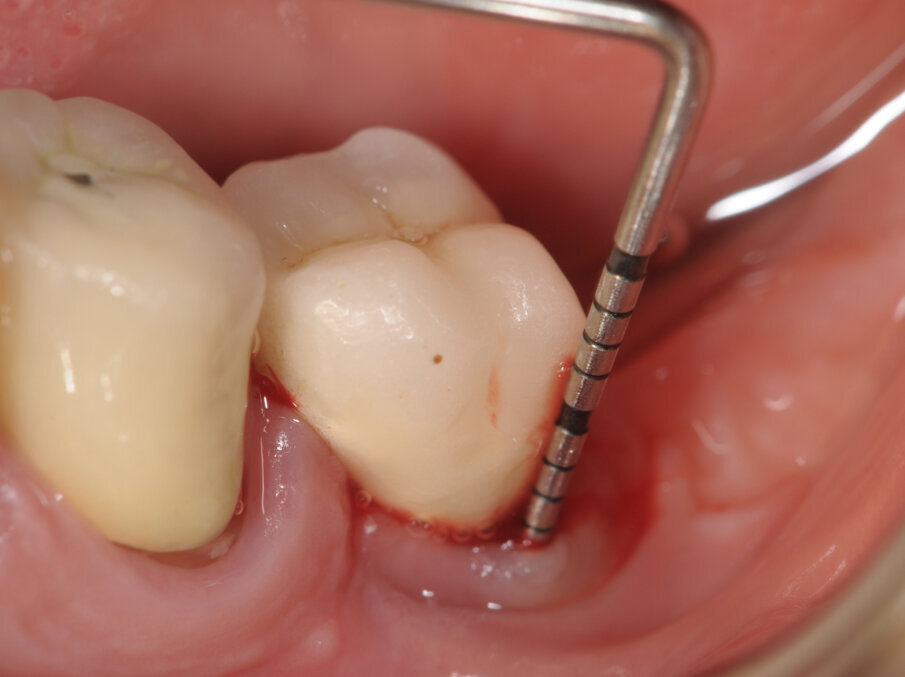

La paziente viene sottoposta alla medesima seduta fatta nei primi 15 giorni con variazione nella frequenza portata ad 1 applicazione per settimana (Figg. 1-6).

A termine del trattamento descritto in precedenza da un punto di vista clinico abbiamo ottenuto un ripristino dei parametri di salute dell’impianto ovvero la scomparsa del sanguinamento dell’edema e della purulenza, in oltre si è verificata una riepitelizzazione dei tessuti molli limitrofi l’impianto. Da un punto di vista radiografico abbiamo ottenuto la neoformazione di osso attorno alle spire dell’impianto (con relativo aumento della stabilità) che a inizio terapia era da considerarsi potenzialmente come perso. La radiografia a 60 gg prima ed a 1 anno mostrano quanto prima descritto, ovvero un ripopolamento di componenti cellulari ossei sull’impianto con un recupero di 3 spire implantari (Figg. 7-9).